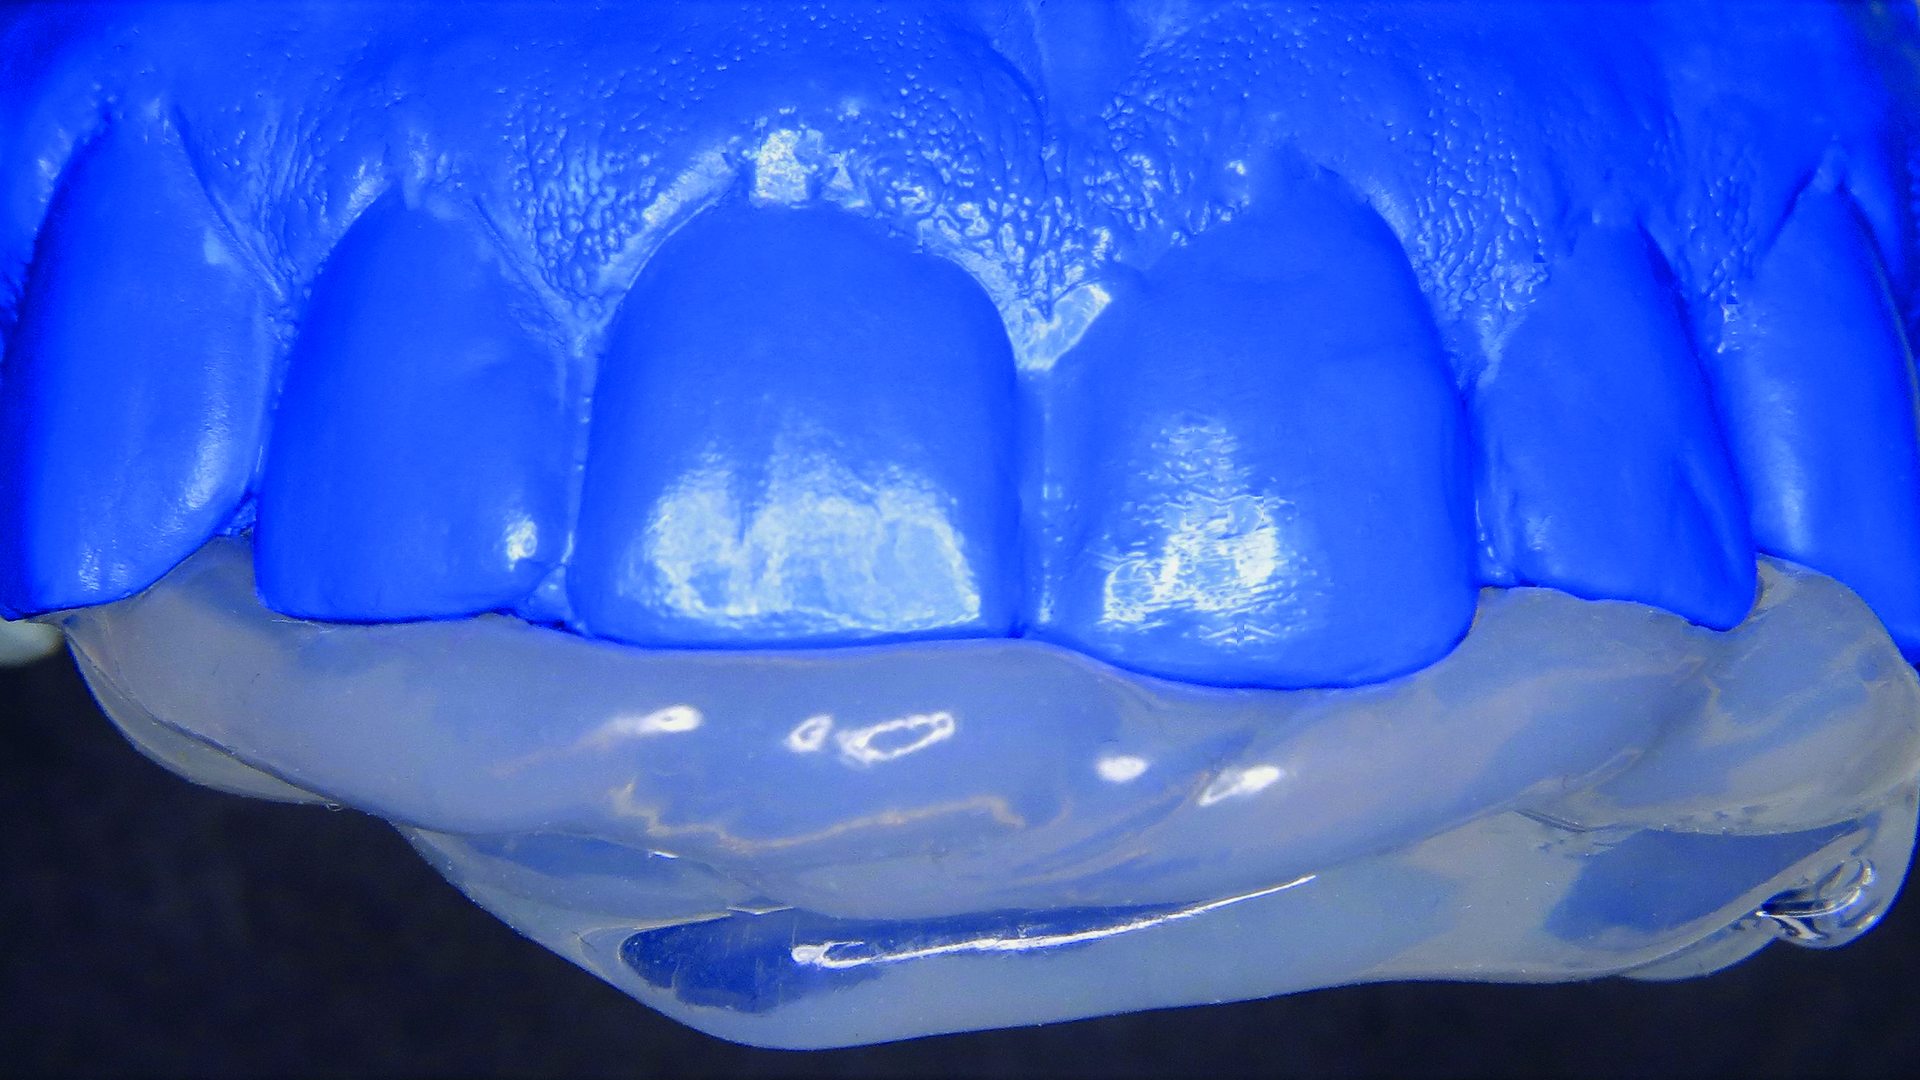

Z gamy odcieni klastrowych wybrano odcień A2 (ryc. 2). Następnie pobrano wycisk masą V-Posil Putty Fast (VOCO GmbH, Niemcy) w celu stworzenia modelu gipsowego. Z materiału Registrado Clear (VOCO GmbH, Niemcy) wykonano indywidualny klucz silikonowy do nadbudowy powierzchni podniebiennej (ryc. 3).

Ryc. 3. Wykonanie indeksu silikonowego.